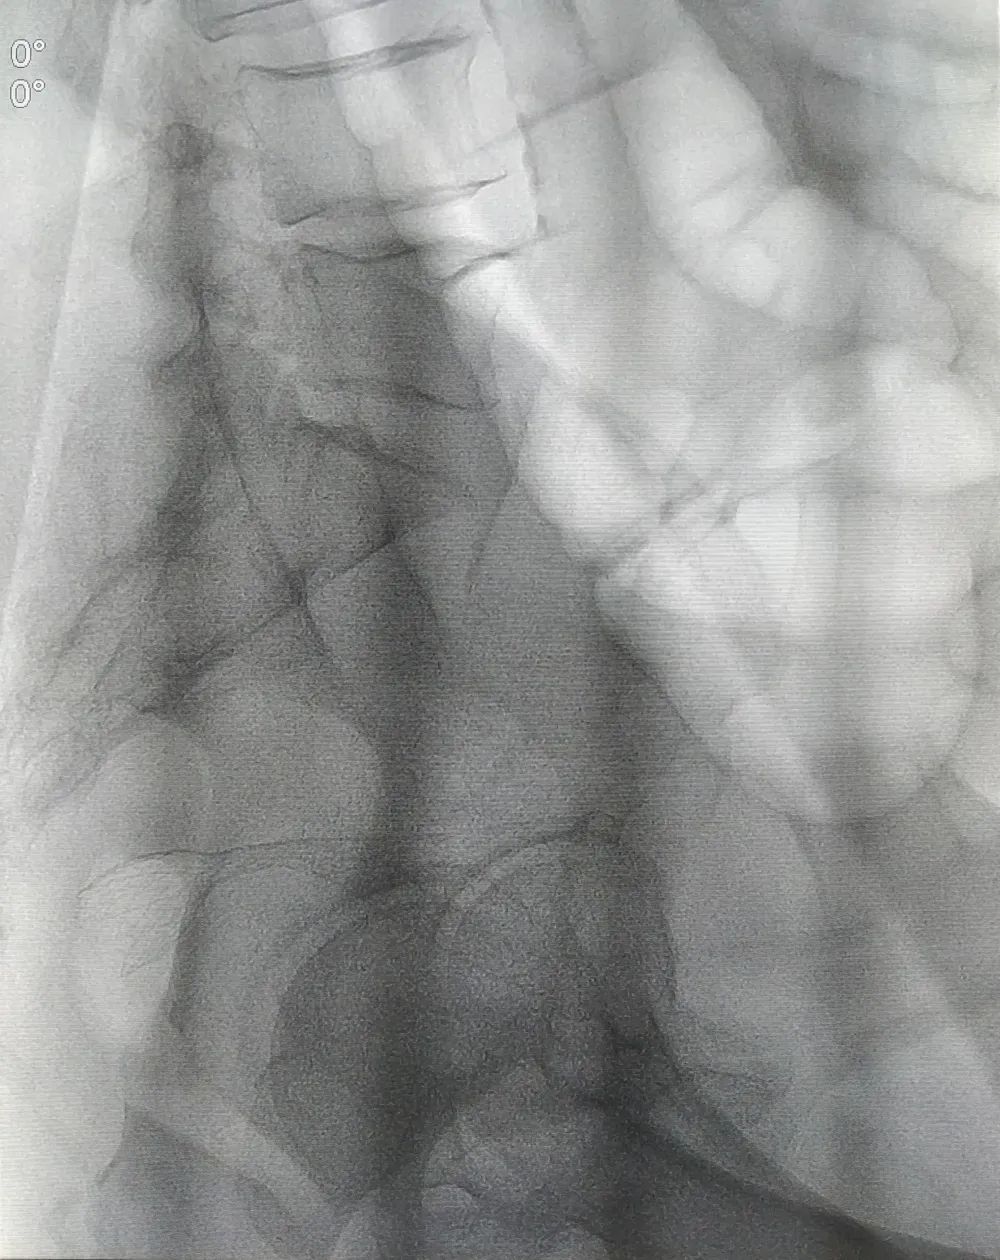

确定诊疗方案后,因患者病情发展较快,消化内科团队为患者开展了急诊肠镜。肠镜检查发现,进镜至距肛缘约 10 cm 处可见一肿物,呈隆起性生长,表面有出血,附有脓苔,考虑直肠恶性肿瘤可能性大,因肠腔水肿、狭窄明显,镜身不能通过,切开刀带导丝进入远端肠道,造影可见肠道呈截断性狭窄。

为快速缓解症状、解除患者疼痛,消化内科郭锐主任及张磊护师结合患者具体情况,决定给予肠道支架置入解除肠道梗阻,使患者免遭肠造瘘的痛苦,为择期手术切除直肠病变做好准备。由于病变导致肠腔严重狭窄,肠道支架置入难度也随之增加,郭锐主任凭借夯实的理论基础及高超的操作技术,通过 DSA 及肠镜联合引导,成功完成了肠道内金属支架置入术。术后患者能自主排便,腹痛、腹胀症状明显缓解,现已出院。

即在肠道狭窄的部位放置一个网状支架将肠道撑开,使狭窄或阻塞部位重新恢复通畅,可作为结直肠癌恶性梗阻的永久或暂时性治疗。肠道支架的过渡性放置,使梗阻性结直肠癌患者的肠道局部和全身状态恢复或接近无梗阻状态,2-3 周后再选择结直肠癌的 I 期手术方式处理,降低造瘘率、改善患者生存质量。肠道支架置入的引导方式有 DSA 引导和肠镜引导,DSA 引导通过注入对比剂能透视到狭窄近段肠腔扩张的程度,以及导丝是否确定在肠腔内;肠镜引导能直接清晰地看到狭窄远段肠腔的情况,尤其是狭窄段外口的具体位置;两者结合对重度狭窄、甚至闭塞的肠腔寻得一丝缝隙,使得支架置入获得成功。